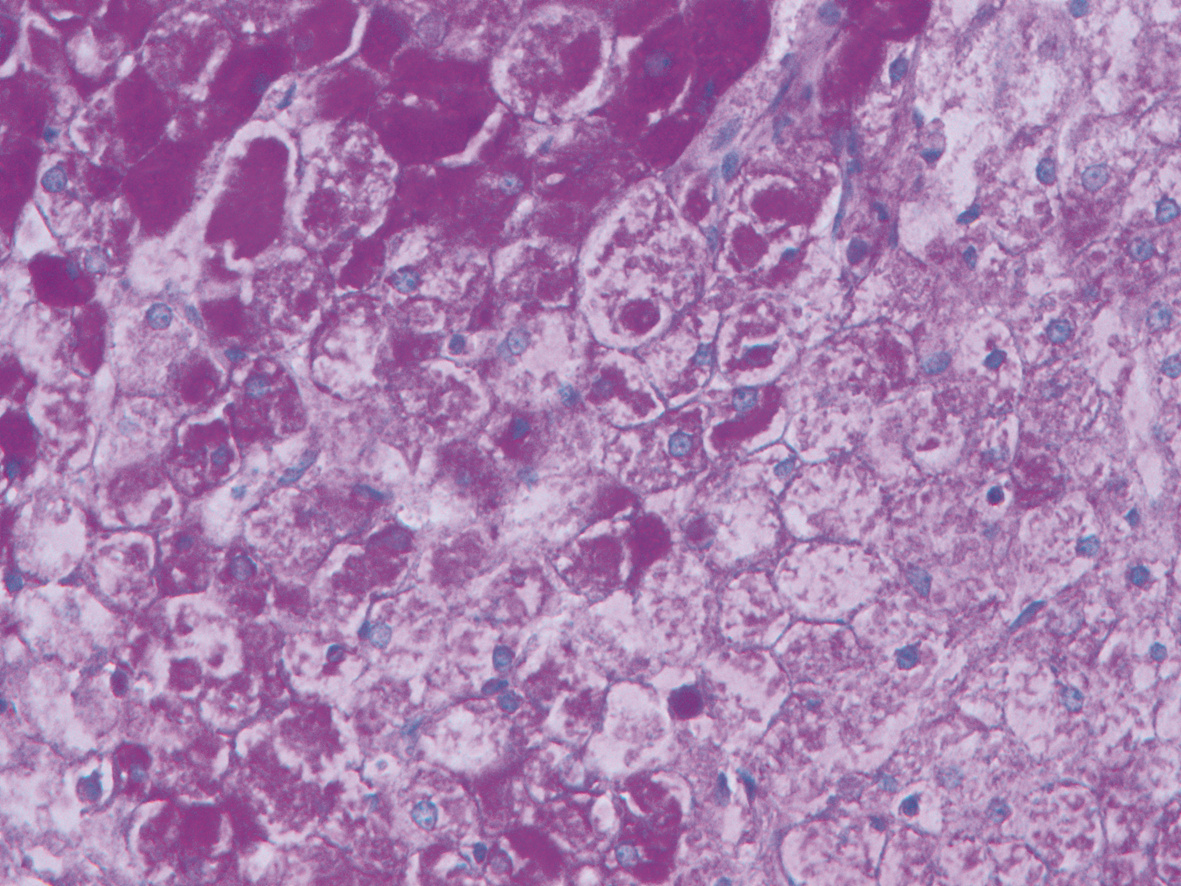

Hepatocellular carcinoma with bile duct tumor thrombus: A case report

Renjie LU, Fangfang SUN, Jie DU, Lirong ZHAO

2022, 38(8): 1872-1874. DOI: 10.3969/j.issn.1001-5256.2022.08.028

Abstract(762) HTML (437) PDF (3665KB)(68)

Abstract: